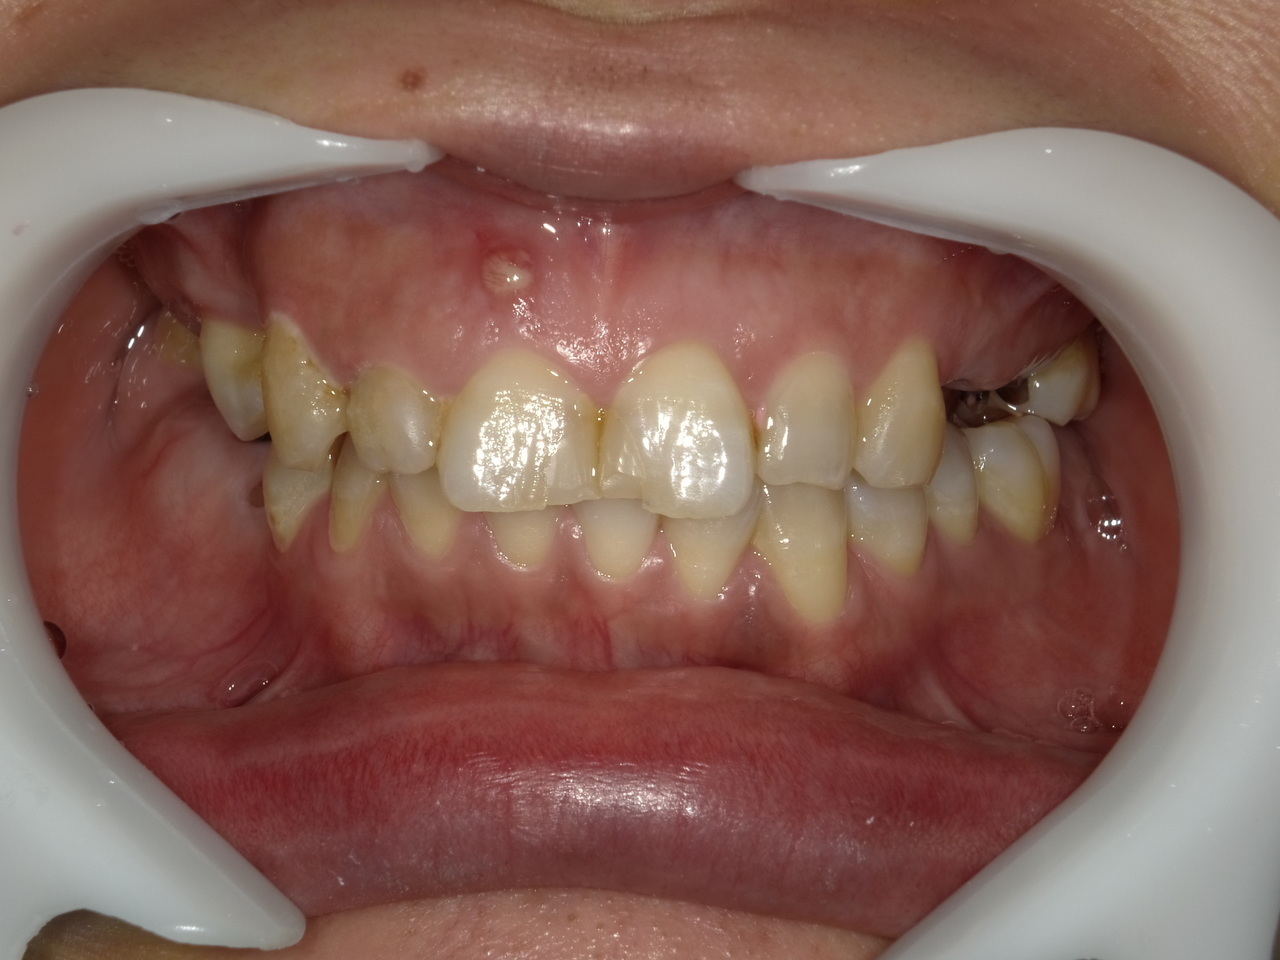

1.左上3番 インプラント抜歯即時埋入即時荷重(手術当日に抜歯を行い、当日に仮歯を入れています。)、左上4番 3ユニット式ブリッジが入るまでの暫間インプラントを埋入して当日に仮歯の装着。 左上5 既存骨3mmのグラフトレスサイナスリフト。最終補綴は、3ユニットジルコニアブリッジで治療を終えた症例

Before

枚方市のインプラントの症例

After

E・S様 女性 60代

患者様の症状としては、左上5番の排膿と重度の歯の動揺、重度の骨吸収、左上3番、中程度の骨吸収と中程度の歯の動揺、自発痛がありました。

治療法としては、左上3456にブリッジ治療が行われていたが、左上5の骨吸収と排膿を認めるために抜歯を行った2か月後に、患者様は、インプラント治療を希望。左上3の骨吸収と動揺も認めていたために、左上3を保存しても将来的な抜歯が予想されたため、左上3抜歯しての左上345の3ユニット式ブリッジ治療の計画を立てインプラント手術を行っています。患者様は、前歯がないことを気にされていたため、左上3番の抜歯と同時の仮歯製作と左上4番暫間インプラントにての仮歯製作を手術と同時に行っています。また、左上3番の歯肉退縮を予防するために、ご自分の歯の一部を温存するルートメンブレンテクニックを行っています。左上5に関しては、既存骨が3mm程度しかないので、グラフトレスサイナスリフトを施行して、表面の骨吸収した部分に骨補填材填入して、ボリュームを維持させていただいています。最終的な3ユニットブリッジは、ジルコニアで製作しています。補綴物の製作に関しては、オールデジタルで行っています。

治療結果は、患者様の希望通り、見えるところの歯がない状態なく、治療を終えることができたことと、また、グラフトレスサイナスリフトを施行することにより、従来のサイナスリフトを施行した場合と比較して、6時か月以上早く治療を終えることができたことと、ルートメンブレンテクニックを行うことで、歯肉退縮を少なくでき、自然な見た目で、最終補綴物を装着できました。従来のGBRやサイナスリフトを行わなかったことにより、短時間で、低侵襲に治療を終えることができ、審美面と機能面の回復を行うことができました。

治療の期間・回数:4か月、10回

治療の価格:814,000円(税込)

治療費の内訳:インプラント基本料(フィックスチャー及び手術費用、投薬費用、レントゲン費用、インプラント上部費用(アバットメントおよびジルコニアクラウンの費用用)右上3番5番 330000円×2 660000円(税込み)オプション費用 右上5グラフトレスサイナスリフト費用 33000円(税込み) 右上3抜歯即時荷重費用 33000円(税込み) 暫間インプラント費用 0円

治療のリスクや副作用:手術後に、痛みや腫れ、出血、合併症などを引き起こす可能性があります。噛む感覚がご自身の歯と異なる場合があります。見た目がご自身の歯と異なる場合があります。手術後にメインテナンスを継続しないと、インプラントが抜け落ちる可能性があります。